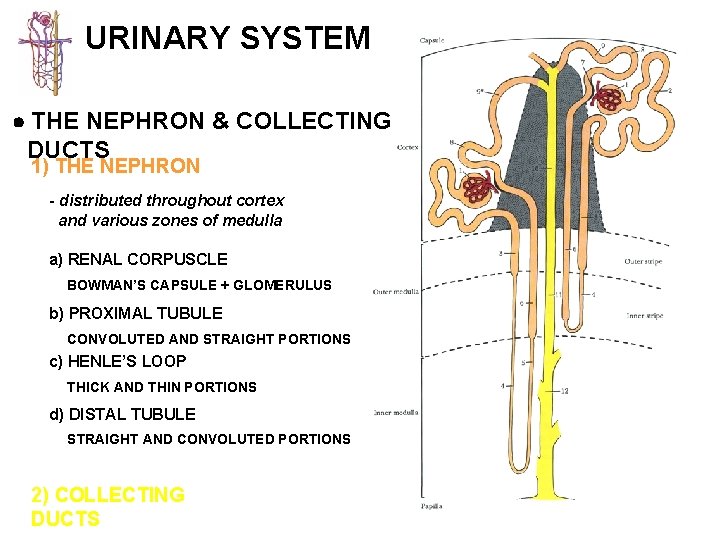

URINARY SYSTEM THE NEPHRON & COLLECTING DUCTS 1) THE NEPHRON - distributed throughout cortex and various zones of medulla a) RENAL CORPUSCLE BOWMAN’S CAPSULE + GLOMERULUS b) PROXIMAL TUBULE CONVOLUTED AND STRAIGHT PORTIONS c) HENLE’S LOOP THICK AND THIN PORTIONS d) DISTAL TUBULE STRAIGHT AND CONVOLUTED PORTIONS 2) COLLECTING DUCTS

URINARY SYSTEM THE NEPHRON & COLLECTING DUCTS CORTEX: CORTICAL LABYRINTH 1 - RENAL CORPUSCLES 2 - PROXIMAL CONVOLUTED TUBULES 3 - DISTAL CONVOLUTED TUBULES MEDULLARY RAY 1 - STRAIGHT PORTIONS OF PROXIMAL TUBULE (THICK DESCENDING) 2 - STRAIGHT PORTIONS OF DISTAL TUBULE (THICK ASCENDING) 3 - COLLECTING DUCTS

URINARY SYSTEM THE NEPHRON & COLLECTING DUCTS MEDULLA: OUTER ZONE 1 - STRAIGHT PORTIONS OF PROXIMAL TUBULE (THICK DESCENDING) 2 - STRAIGHT PORTIONS OF DISTAL TUBULE (THICK ASCENDING) 3 - THIN SEGMENTS OF LOOP OF HENLE (DESCENDING & 4 -ASCENDING) COLLECTING DUCTS INNER ZONE 1 - THIN SEGMENTS OF LOOP OF HENLE (DESCENDING & 2 -ASCENDING) COLLECTING DUCTS